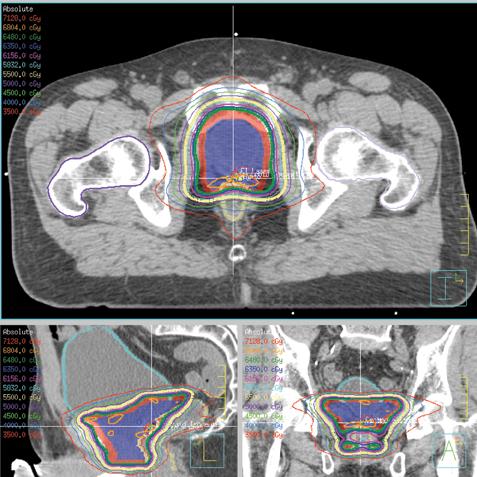

The general approach has come to be known as volumetric modulated arc therapy (VMAT). The biggest appeal of VMAT is the reduction in treatment times compared to traditional IMRT, since there is no wasted time, as gantry rotation, MLC movement and radiation delivery all happen simultaneously. (See Figure 1, which shows an axial view of a VMAT plan for prostate cancer treatment.)